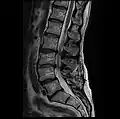

MRI lumbar spine with degeneration, post-hemilaminectomy L4-5 (sagittal T2 FRFSE)